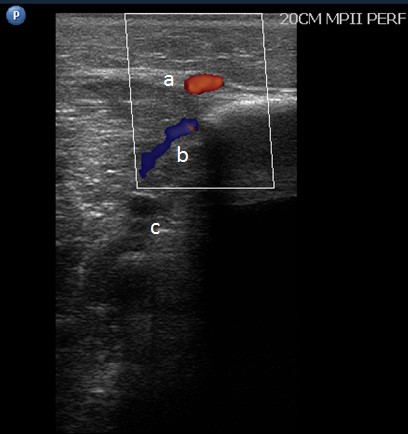

Sistema de venas perforantes. Son vasos de un diámetro que no debe superar los 3 mm. Atraviesan la aponeurosis muscular y comunican el sistema venoso superficial con el sistema venoso profundo, mediante un sistema valvular que en condiciones normales permite el drenaje de sangre en ese sentido. La forma de cono truncado, con el orifico externo menor que el interno favorece direccionar el flujo desde el sistema superficial al profundo (4) (Fig. 3 y Fig. 4).

Las venas perforantes se diferencian en: directas, que comunican el sistema venoso profundo con las venas safenas; e indirectas, que lo comunican con alguna vena tributaria. Cuando se invierte el flujo de la perforante por in-suficiencia venosa, se denominan “perforantes de fuga”, esta es una condición anormal, que requiere tratamiento, las perforantes de reentrada compensan a las de fuga, tienen dirección normal (4).

Se dibujan las venas perforantes y comunicantes insuficientes que presenten un diámetro mayor a 3,5 mm, más una evaluación de la dirección del flujo para determinar si son de fuga o de reentrada, y la presencia de reflujo al Doppler pulsado. Se mide la distancia desde el piso hasta el sitio donde perfora la aponeurosis o donde drena en la vena principal, en caso de ser tributaria; tam-bién se pueden agregar las teleangiectasias, venas tegumentarias, úlceras o cambios tróficos en la piel (Fig. 18). Se utiliza el color azul para indicar las venas competentes y el rojo para las insuficientes (17, 18).